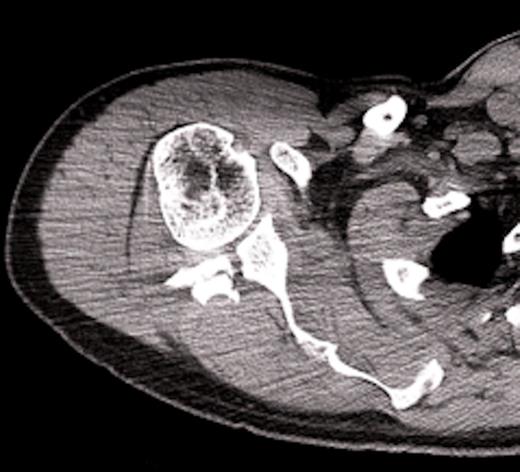

On examination there was restriction of the range of movement of the right shoulder with tenderness and swelling over the scapular. The skin was intact. There was no neurovascular deficit and the patient was otherwise physically well. X-rays revealed a fracture of the body of the scapula with posterior displacement of the inferior fragment. The shoulder joint was not dislocated and there were no associated fractures of the proximal humerus. The patient was admitted for analgesia and computed tomography was performed to assess the fracture. The scan showed involvement of the glenoid, with the fracture extending through the posterior lip. This was deemed inappropriate for surgical fixation. The patient was managed in a broad arm sling and discharged with simple range of movement exercises.

Computed tomographic scan with 3D reconstruction showing the scapula fracture